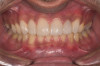

Examination revealed that palatal surfaces of teeth Nos. 6 through 11 showed severe loss of tooth structure, with mild wear on the lower incisors and loss of anterior guidance (Figure 5 through Figure 7). The palatal TSL was consistent with the clinical picture presented by patients with gastric reflux. A detailed medical history was taken, and the patient complained of having heartburn and acidity at least 4 out of 7 days a week. He had never sought treatment for it and used over-the-counter medication when needed. He was a nonsmoker, with occasional intake of alcohol. He had a high-stress job with irregular meal times. A thorough smile and dental analysis11 was carried out; the findings appear in Table 2.